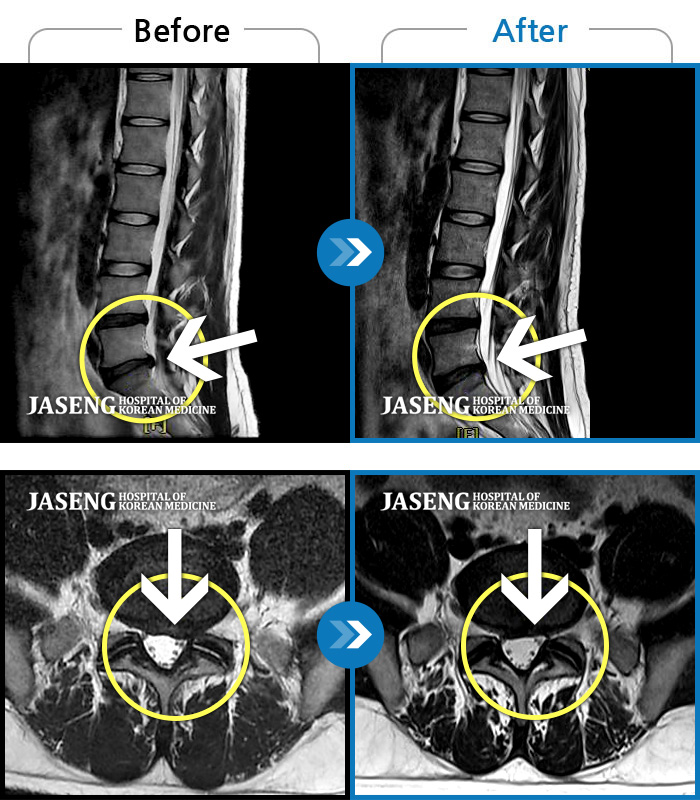

Before

After

좌측 허리 통증으로 허리를 반듯이 펴고 서있기 힘들어 내원하셨습니다.

2024.08.12 ~ 2025.02.26